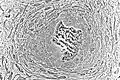

Osteoblasts (purple) rimming a bony spicule (pink - on diagonal of image). In this routinely fixed and decalcified (bone mineral removed) tissue, the osteoblasts have retracted and are separated from each other and from their underlying matrix. In living bone, the cells are linked by tight junctions and gap junctions, and integrated with underlying osteocytes and matrix H&E stain. | |